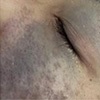

在众多皮肤表现中,太田痣因其独特的分布位置和颜色特征,常常引起关注。它通常呈现为蓝灰色或青褐色的斑片,多出现在面部一侧的眼周、颧骨或颞部区域。虽然这种胎记本身并不带来明显不适,但其出现并非随机,而是与某些先天因素密切相关。了解哪些人群更容易出现太田痣,有助于提前识别并合理应对。

这种胎记的形成与胚胎发育过程中特定细胞的迁移异常有关,因此在不同个体中的表现存在规律性差异。太田痣更偏爱这类人群,这 3 个特征要留意——这一说法并非空穴来风,而是基于长期观察总结出的共性倾向。首先,性别是一个值得关注的因素:女性出现太田痣的比例明显高于男性。其次,肤色较深的人群,尤其是东亚、东南亚及部分非洲裔背景的个体,发生率相对更高。最后,家族中若曾有类似表现,后代出现的可能性也会增加。这三个特征虽不能作为绝对判断依据,却提供了重要的参考方向。

太田痣更偏爱这类人群,这 3 个特征要留意,尤其当多个特征同时存在时,更应保持适度关注。例如,一位年轻女性,肤色偏深,且家族中有长辈曾有类似面部色素表现,那么她在成长过程中出现太田痣的概率可能高于平均水平。当然,这并不意味着必然发生,而是提示一种潜在倾向。关键在于早期识别其典型表现:边界不清、颜色均匀、随年龄缓慢加深,且多局限于单侧面部。